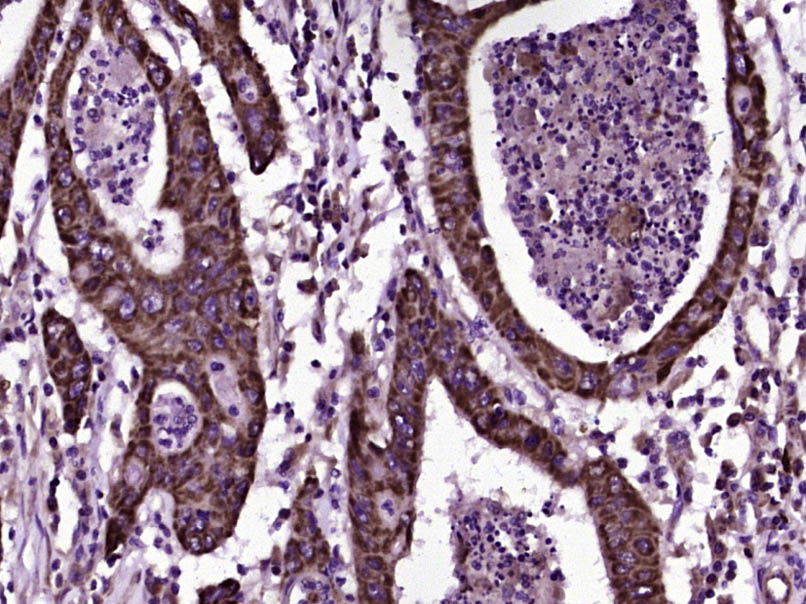

IHC-P analysis of human colon carcinoma tissue using GTX51679 CD200 antibody.

Dilution : 1:200